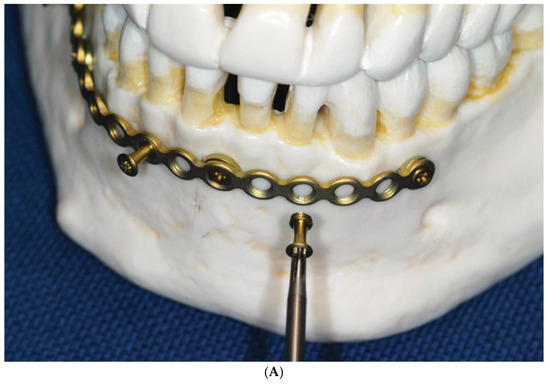

2.3. Matrix Wave System—Final Design and Technical Description

3.1. Matrix Wave Plate—Segmentation and Malleability

3.2. Matrix WaveTM Plate MMF System—Mode of Application